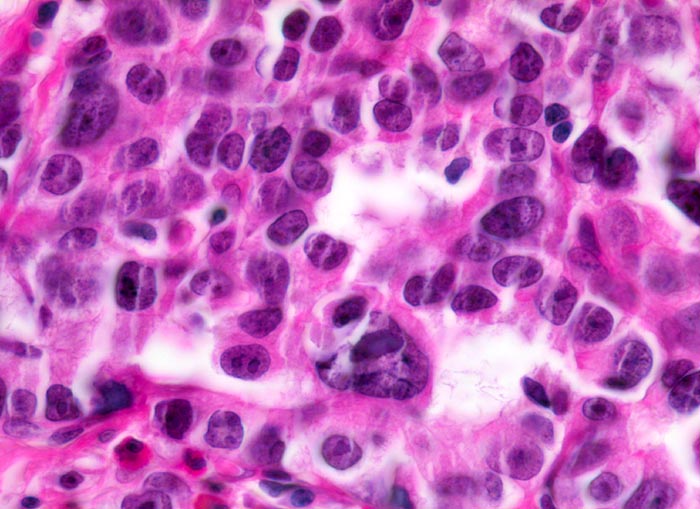

Weiter oben Invasion der Magenschleimhaut durch ein teils solides, teils drüsenbildendes Adenokarzinom mit stark atypischen Tumorzellen.

Der invasive Karzinomanteil zeigt teilweise muzinöse Differenzierung (teils siegelringzellige Tumorzellen schwimmen in extrazellulären Schleimseen).